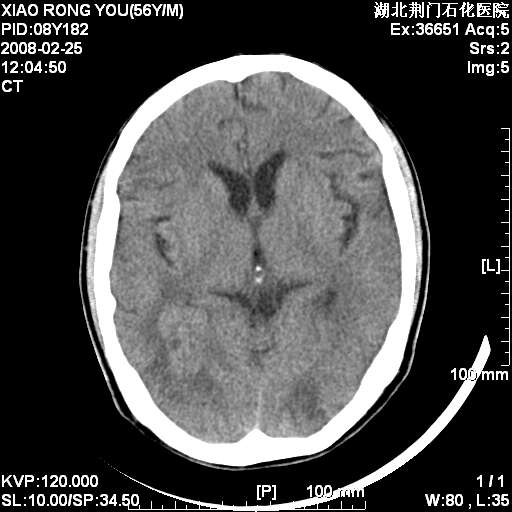

男性,68岁,多年肺结核病史。最近ct复查右肺有占位。

头部平扫